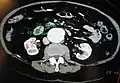

Transverse section through the middle of the first lumbar vertebra, showing the relations of the pancreas. CT scan showing the liver and a kidney

CT scan showing the liver and a kidney A transverse contrast enhanced CT scan demonstrating an abdominal aortic aneurysm of 4.8 by 3.8 cm